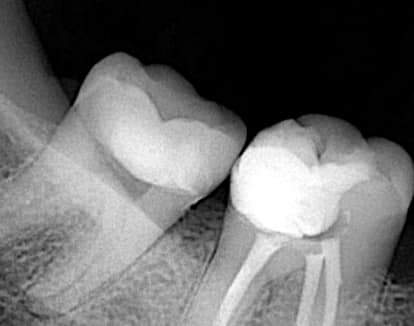

Post operative x ray show the fitness of the restoration , it looks like real part of the tooth ✌️